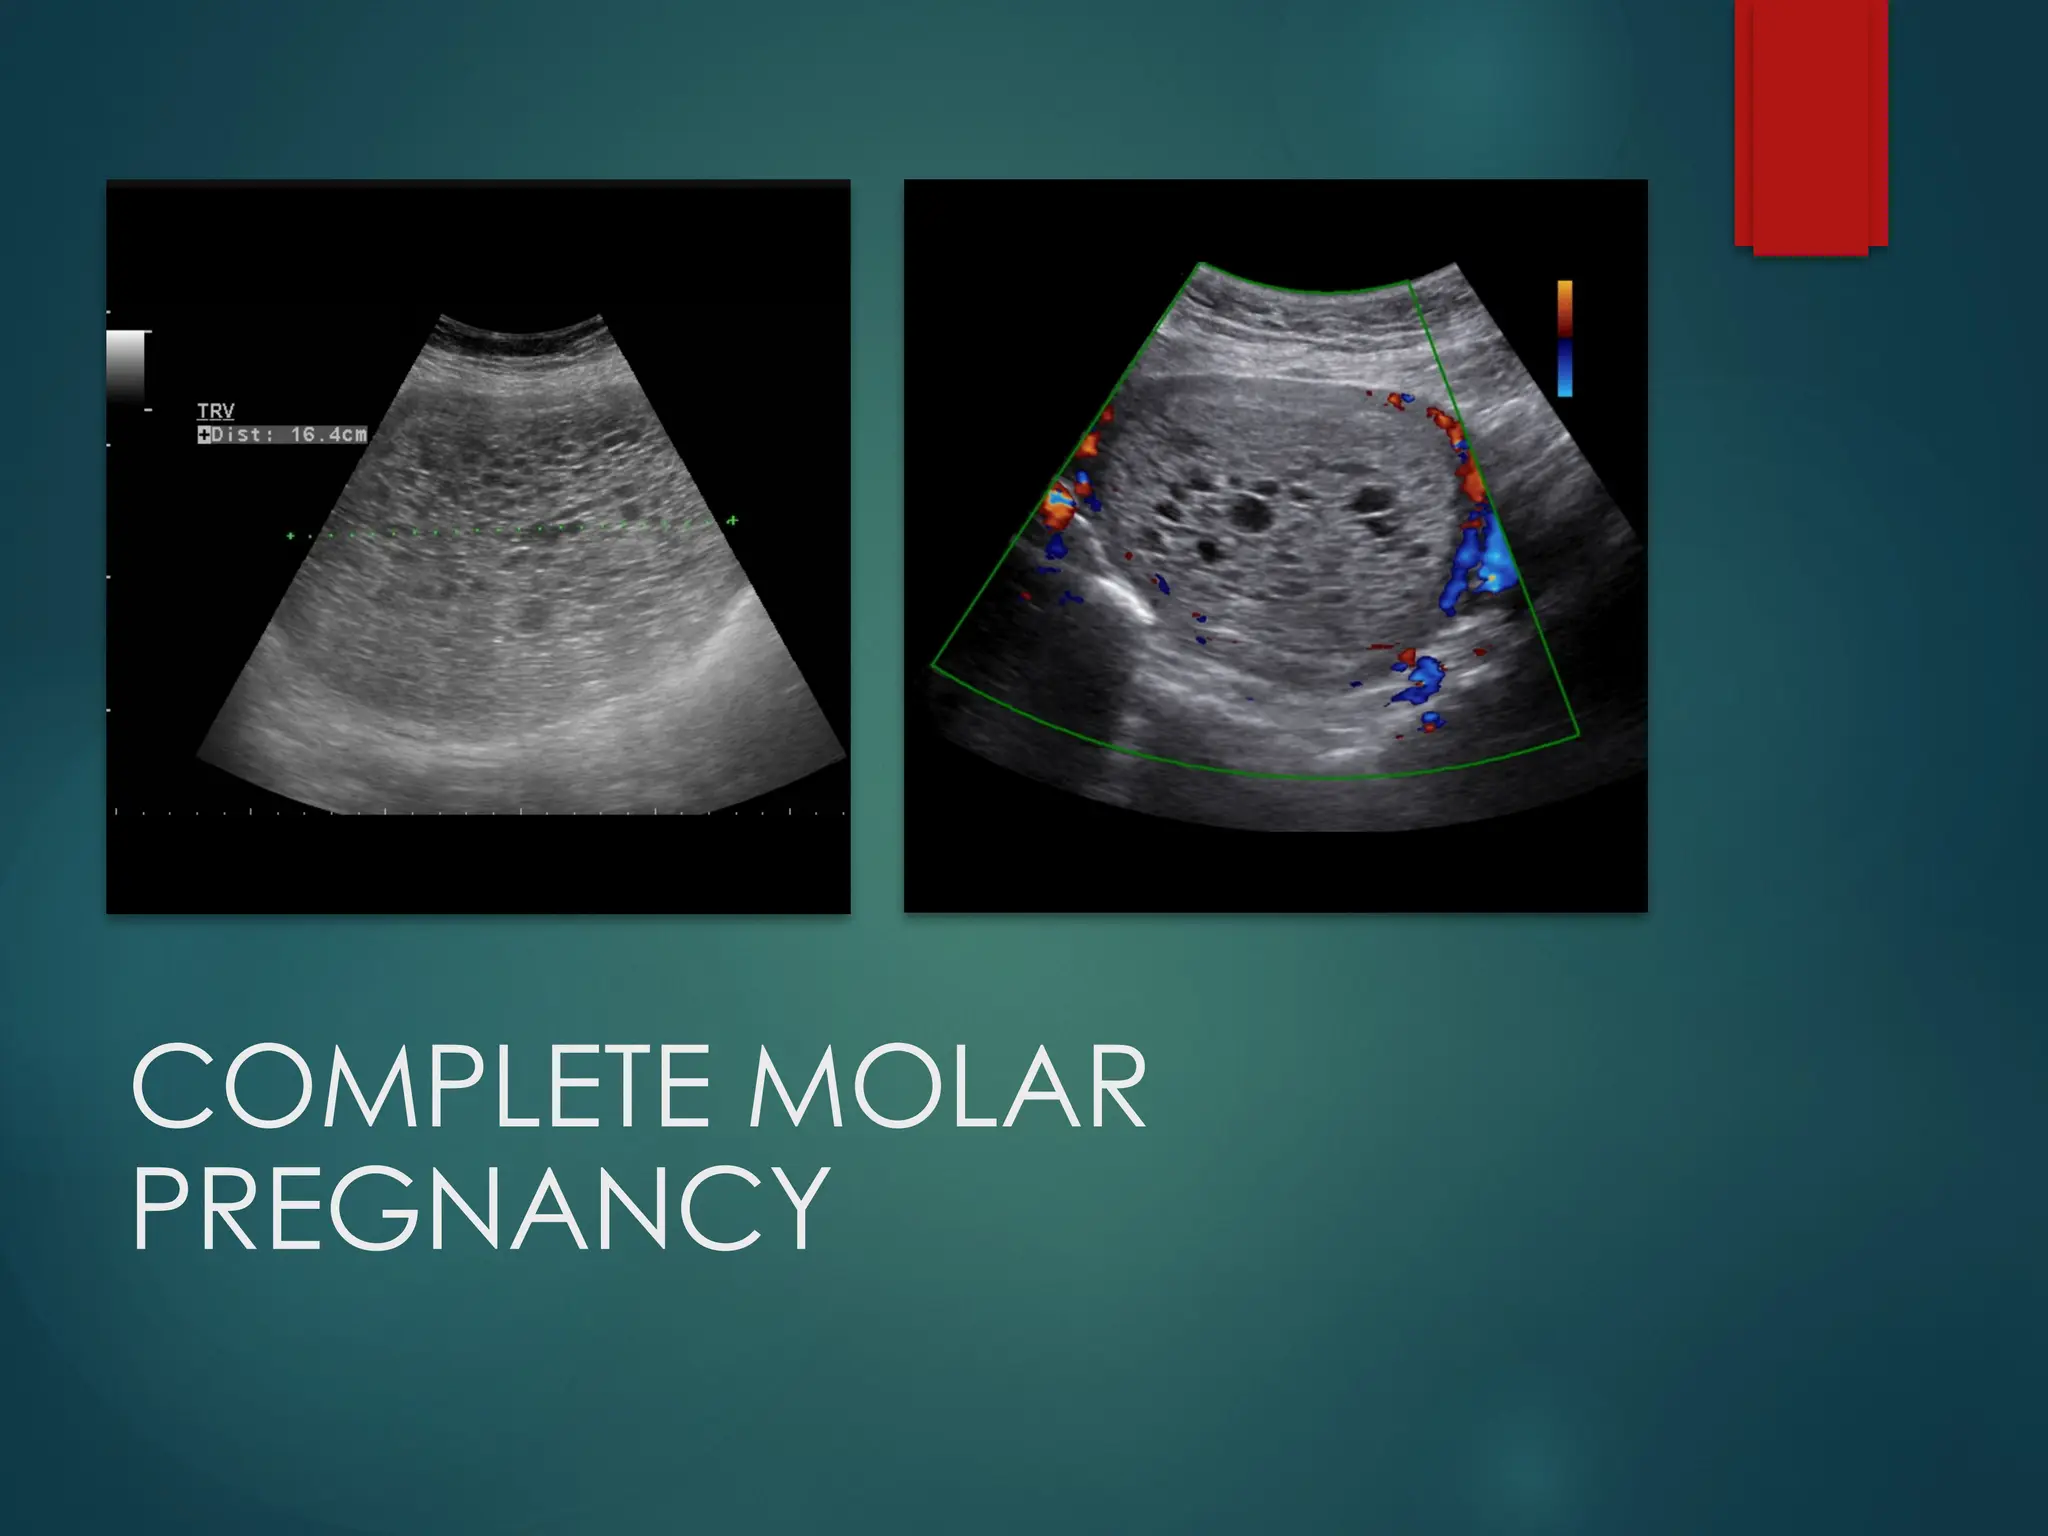

Complete

Molar

Pregnancy

 Enlarged uterus

 Intrauterine mass with multiple

cystic spaces without any

associated of foetal part or foetal

echoes often refer to as

“snowstorm” or “bunch of

grapes” appearance

 Colour doppler shows high

velocity with low impedance flow

COMPLETE MOLAR

Complete Molar Pregnancy  Enlarged uterus Intrauterine mass with multiple cystic spaces without any associated of foetal part or foetal echoes often refer to as “snowstorm” or “bunch of grapes” appearance  Colour doppler shows high velocity with low impedance flow